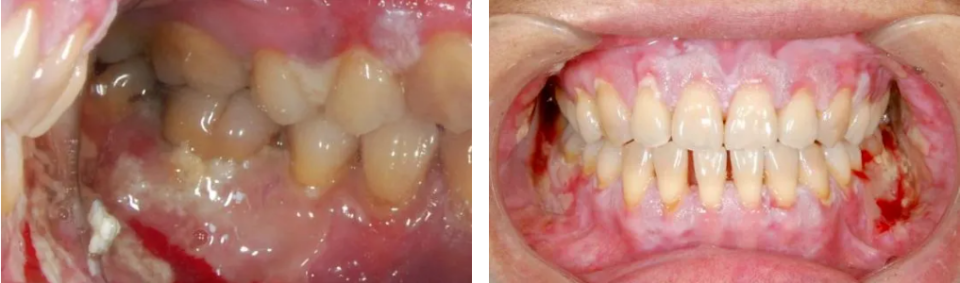

1、疼痛与出血

黏膜的炎症、糜烂与溃疡是疼痛的直接来源,约96.2%的口腔cGVHD患者主诉疼痛7,严重干扰咀嚼、吞咽和言语功能。当溃疡累及唇部等血管丰富的区域时,易导致反复出血,进一步加剧患者的身心负担。研究显示,影响患者口腔健康相关生活质量(OHRQoL)的主要因素是口腔疼痛与敏感症状,而非美国国立卫生研究院口腔黏膜评分量表(NIH OMS)8,提示患者的痛苦感受可能远超临床体征的“直观表现”。

cGVHD口腔表现:红斑、苔藓样损害、溃疡及假膜形成(图片源自陶人川教授团队)

cGVHD黏膜出血表现(图片源自陶人川教授团队)